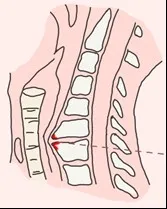

类型6:食管压迫型颈椎病

由于前纵韧带钙化和骨刺形成,导致椎体前缘鸟嘴样增生,压迫食管引起异物感、吞咽困难等症状,经食管钡剂检查可证实。

由于前纵韧带钙化和骨刺形成,导致椎体前缘鸟嘴样增生